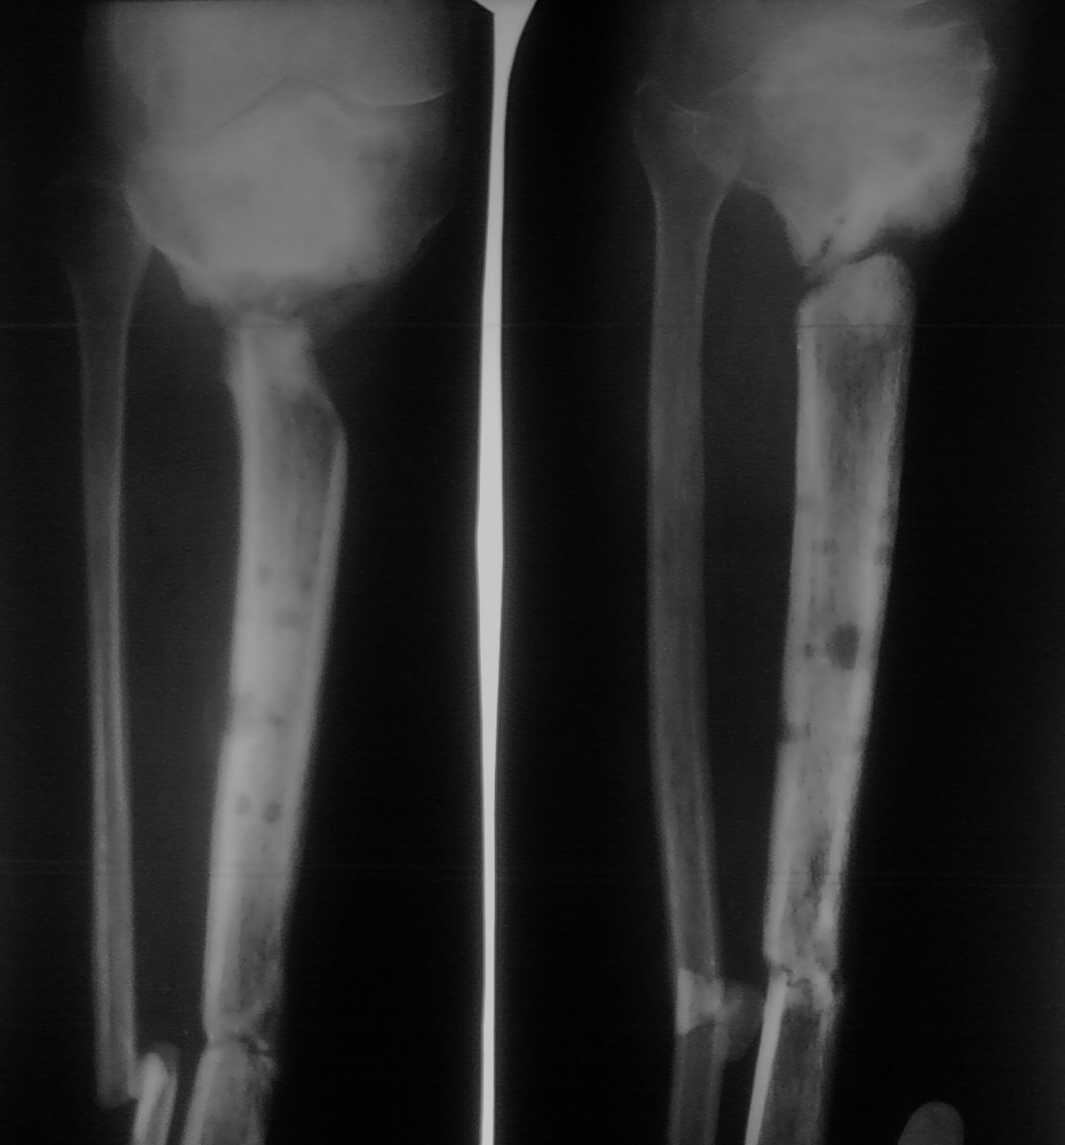

Уважаемые коллеги!Помогите определиться с тактикой лечения пациента с застарелым переломом голени

Больной лечится уже год. Первоначально был открытый перелом дистальной части костей голени и закрытый - в проксимальной части большеберцовой кости. Больного вели на аппарате внешней фиксации. Результат - на снимке.Какую тактику лучше избрать в данном случае?

приветствую , колллеги ! мне кажется , что имеется атрофический ложный сустав голени В данной ситуации не обойтись без стимуляции регенерации костной ткани . стоит иссечь зону атрофии ,наложить аппарат , с последующим транспортом фрагмента . Либо пойти (если получится) на острое укорочение сегмента (до 5 см)с последующим его удлинением (Бедра ? голени ? )

Судя по Р-граммам ситуация очень сложная.

Судя по склерозу среднего фрагмента, кровоснабжение его значительно снижено или отсутсвует. В данной ситуации возможно несколько вариантов: удаление мертвой кости с замещением костного дефекта одним из способов (костный трансплантат на сосудистой ножке, тибиализация малоберцовой кости или перемещение отщепленного костного фрагмента большеберцовой кости) с последующим наложением аппарата внешней фиксации.Или с помощью аппарата внешней фиксации с помощью аккордного метода (чередование компрессии и дистракции) добиваться сращения, а зетем ждать что будет происходить с мертвой кость (или ничего, или будут формироваться свищи, что потребует оперативного удаления мертвой кости)

Будь это мой пациент, я бы начал с аппарата - восстановил бы ось в проксимальном отделе и дал бы там компрессию до сколачивания. Длину если надо восстанавливать, то сделали бы это в дистальном отделе, ниже бывшего перелома на 2-3 см. Кстати говоря, лучше снимки показывать с обоими суставами, а то, может, там еще какая-то неожиданность.

После завершения аппаратных перемещений заштифтовали бы закрыто.

Сращение отсутствует в верху и внизу. Воспользовался бы аппаратом внешней фиксации спизевой компановки и аутопластика на двух уровнях, с погружением импланта в кость (в в/3 наверно бы установил трансплантат с обеих сторон).